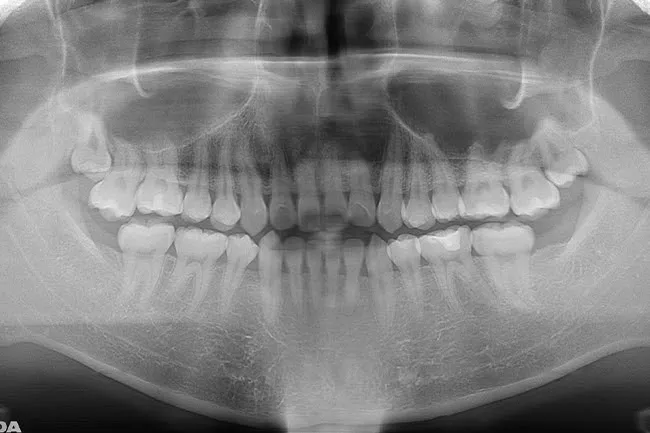

親知らずのある口腔内

親知らずは、大人の歯の中でもっとも奥に生えてくる8番目の歯です。正式名称は、第三大臼歯といい、「智歯(ちし)」とも呼びます。

一般的に親知らずは15歳前後で生えてきますが、20代前半になってから生え始めることも(参照:厚生労働省 e-ヘルスネット「親知らず」より)。お口の中を保護者の方がみる機会が少なくなる時期で、歯が生えたことを知られることがないことから「親知らず」という名前がついています。

上の左右奥に1本ずつ、下の左右奥に1本ずつと最大で合計4本生えてきます。ただし、必ず生えてくるわけではなく、生まれつき親知らずがない方や、1~2本だけ生えてくる方もおり、個人差があるのが特徴です。